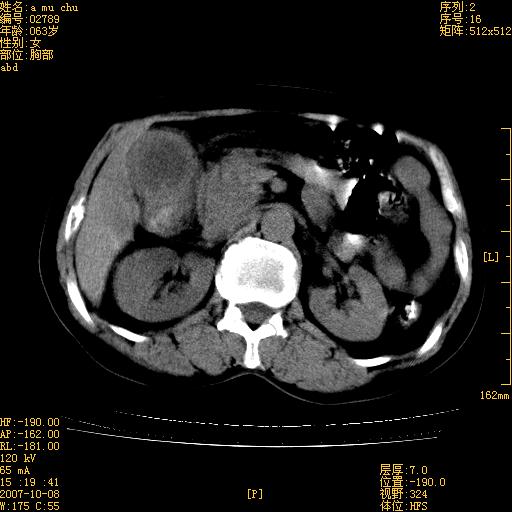

以下是引用王维浦在2007-10-17 21:02:00的发言:[br]胆囊增大,囊壁明显不规则增厚,邻近肝组织浸润,肝内外胆管无扩张。诊断:胆囊ca;[br]胰头软组织肿块影,考虑是由转移肿大的胰后淋巴结、没有肠道准备的十二指肠及胰头共同形成。[br]

以下是引用zhangzexing在2007-10-18 7:13:00的发言:[br]支持胰头占位,慢性胆囊炎. 2.肝左叶前外侧段占位,血管瘤?建议增强

以下是引用影像实习生在2007-10-17 19:49:00的发言:[br]支持胰头占位,慢性胆囊炎. 2.肝左叶前外侧段占位,血管瘤?建议增强.

以下是引用刘振江在2007-10-17 19:42:00的发言:[br]没有增强,胰头癌?胆囊及肝左叶占位?